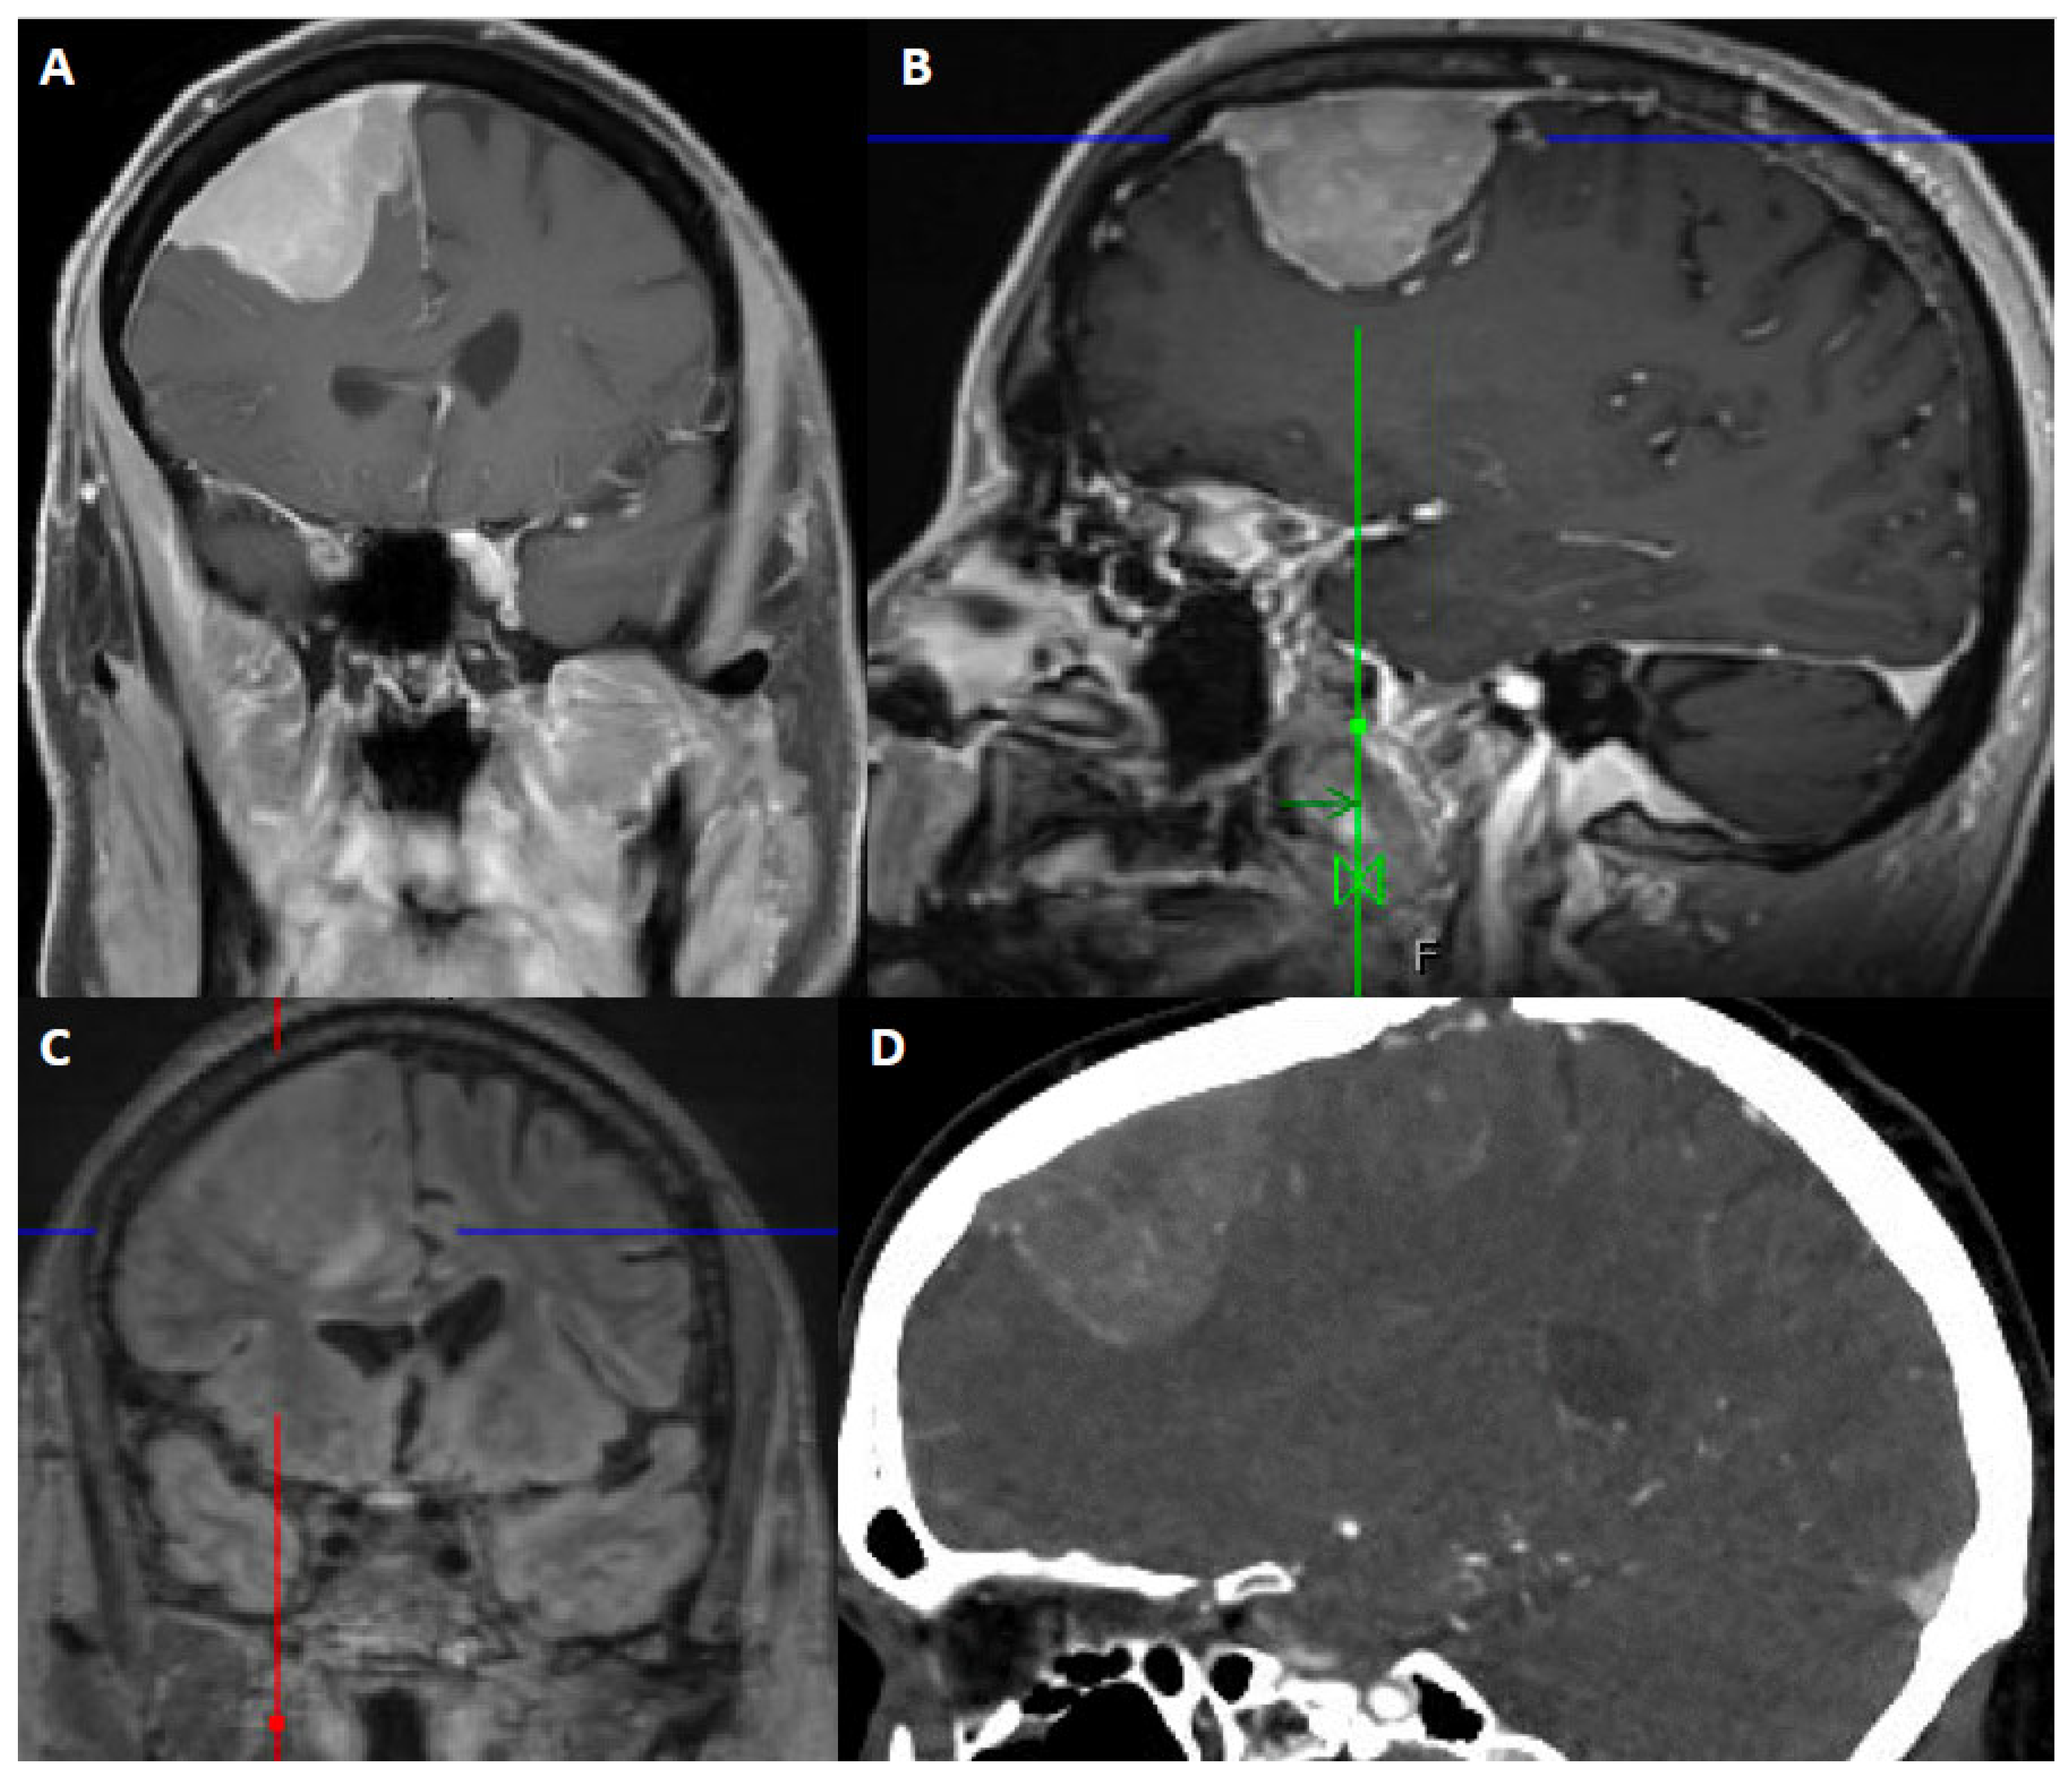

6. Imaging

- Villanueva-Meyer, J.E. Modern Day Imaging of Meningiomas. In Handbook of Clinical Neurology; Elsevier: Amsterdam, The Netherlands, 2020; Volume 169, pp. 177–191. [Google Scholar]